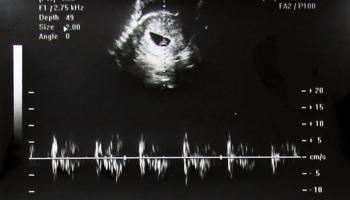

1. 임신 12주 차 - 2.88cm